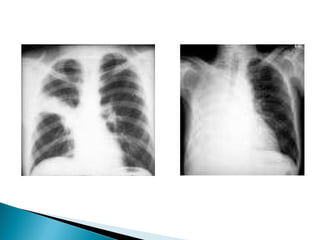

2.1 – Póstero-anterior (PA)

2.2 – Ântero-posterior (AP)

2.3 – Perfil

2.5 – Decúbito lateral com raios

horizontais (Laurell)